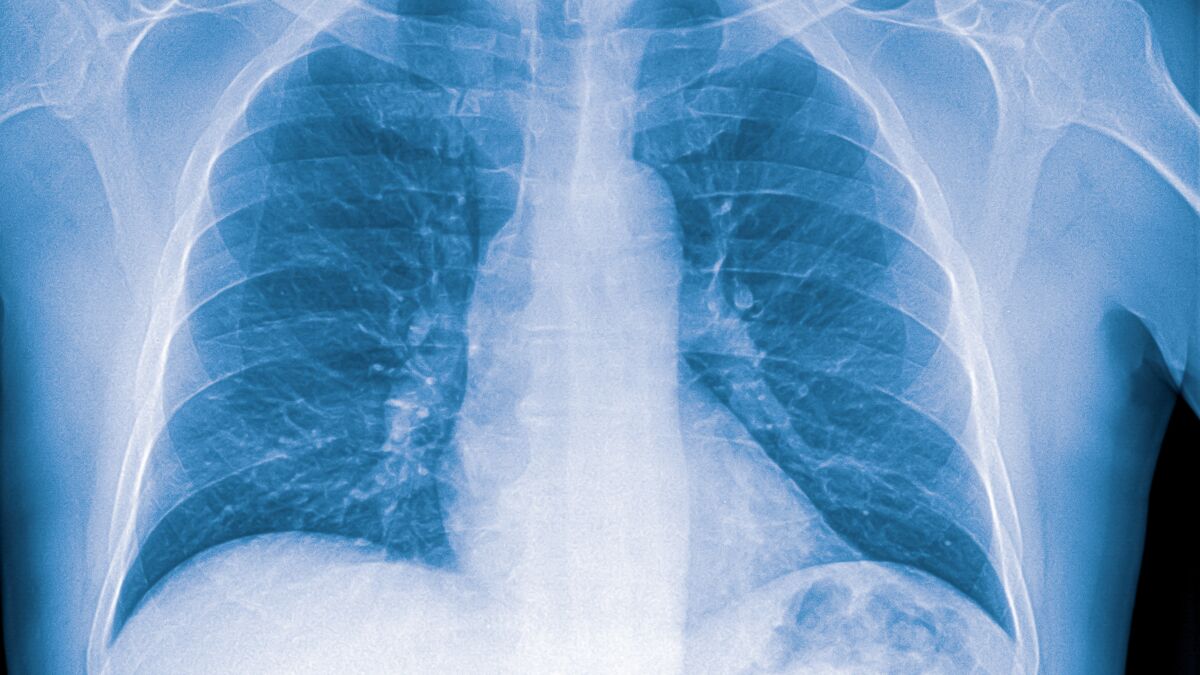

Silicose : une pathologie qui peut entrainer l’invalidité et la mort

Le médecin revient ici sur les signes cliniques de la silicose. Oriane HOUNKPE qu’on écoute à nouveau